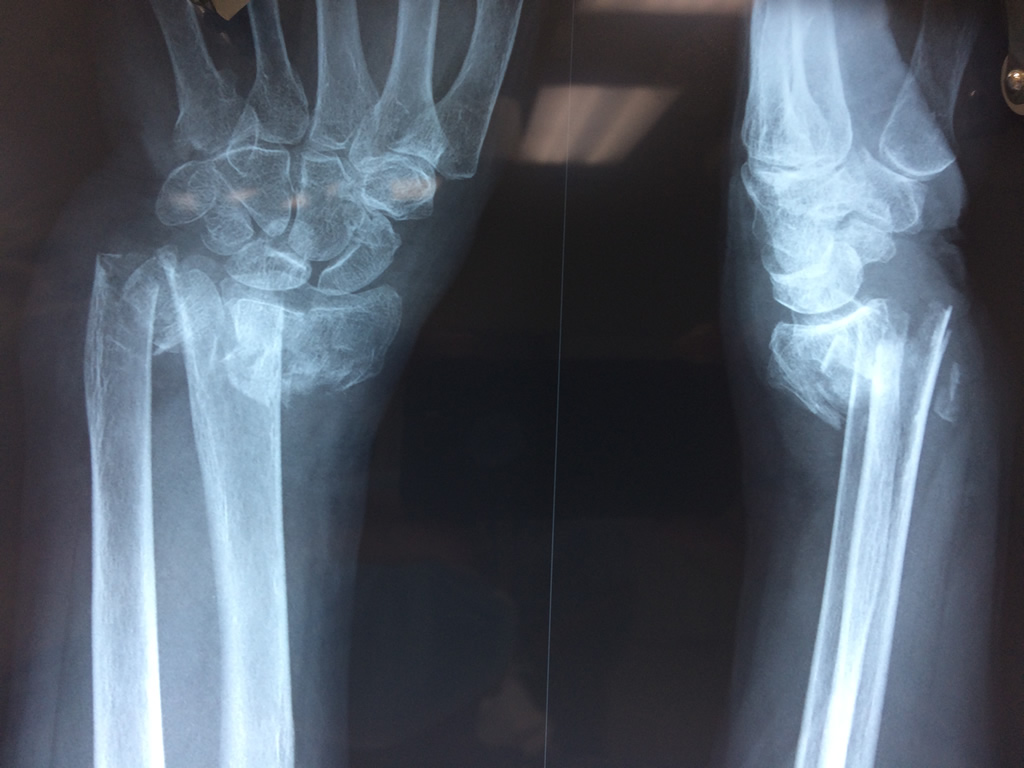

Calcaneo - Cirugías de Muñecas y Manos

Los procedimientos más comunes en cirugía de la mano son aquellos destinados a reparar traumatismos, incluyendo lesiones de tendones, nervios, vasos sanguíneos, y articulaciones; huesos fracturados; y quemaduras, cortes, y otros daños de la piel.